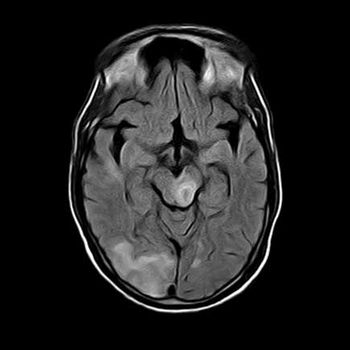

Case History: A 65-year-old patient with history of altered behavior and memory loss for 15 days